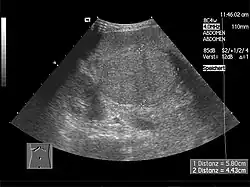

Základem diagnostiky je podrobná anamnéza, objektivní vyšetření a výsledky biochemických vyšetření. Dále se běžně provádí sonografické vyšetření jater a dopplerovské sonografické vyšetření jaterních cév. Pokud je potřeba objasnit příčinu cirhózy, nebo určit její staging a grading, provádí se perkutánní jaterní biopsie, popřípadě transjugulární biopsie. U každého nemocného je třeba vyšetřit jícen a žaludek k průkazu varixů.